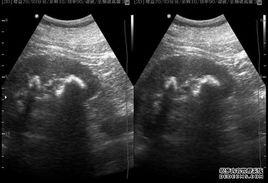

腎結石分為單發和多發,單發就是只是一個結石,無用論大小,而多發性雙腎結石就是雙側腎臟都發現多個結石(超過2個以上),總之來說,多發性雙腎結石還是屬於腎結石,只是區分於單髮結石而已。